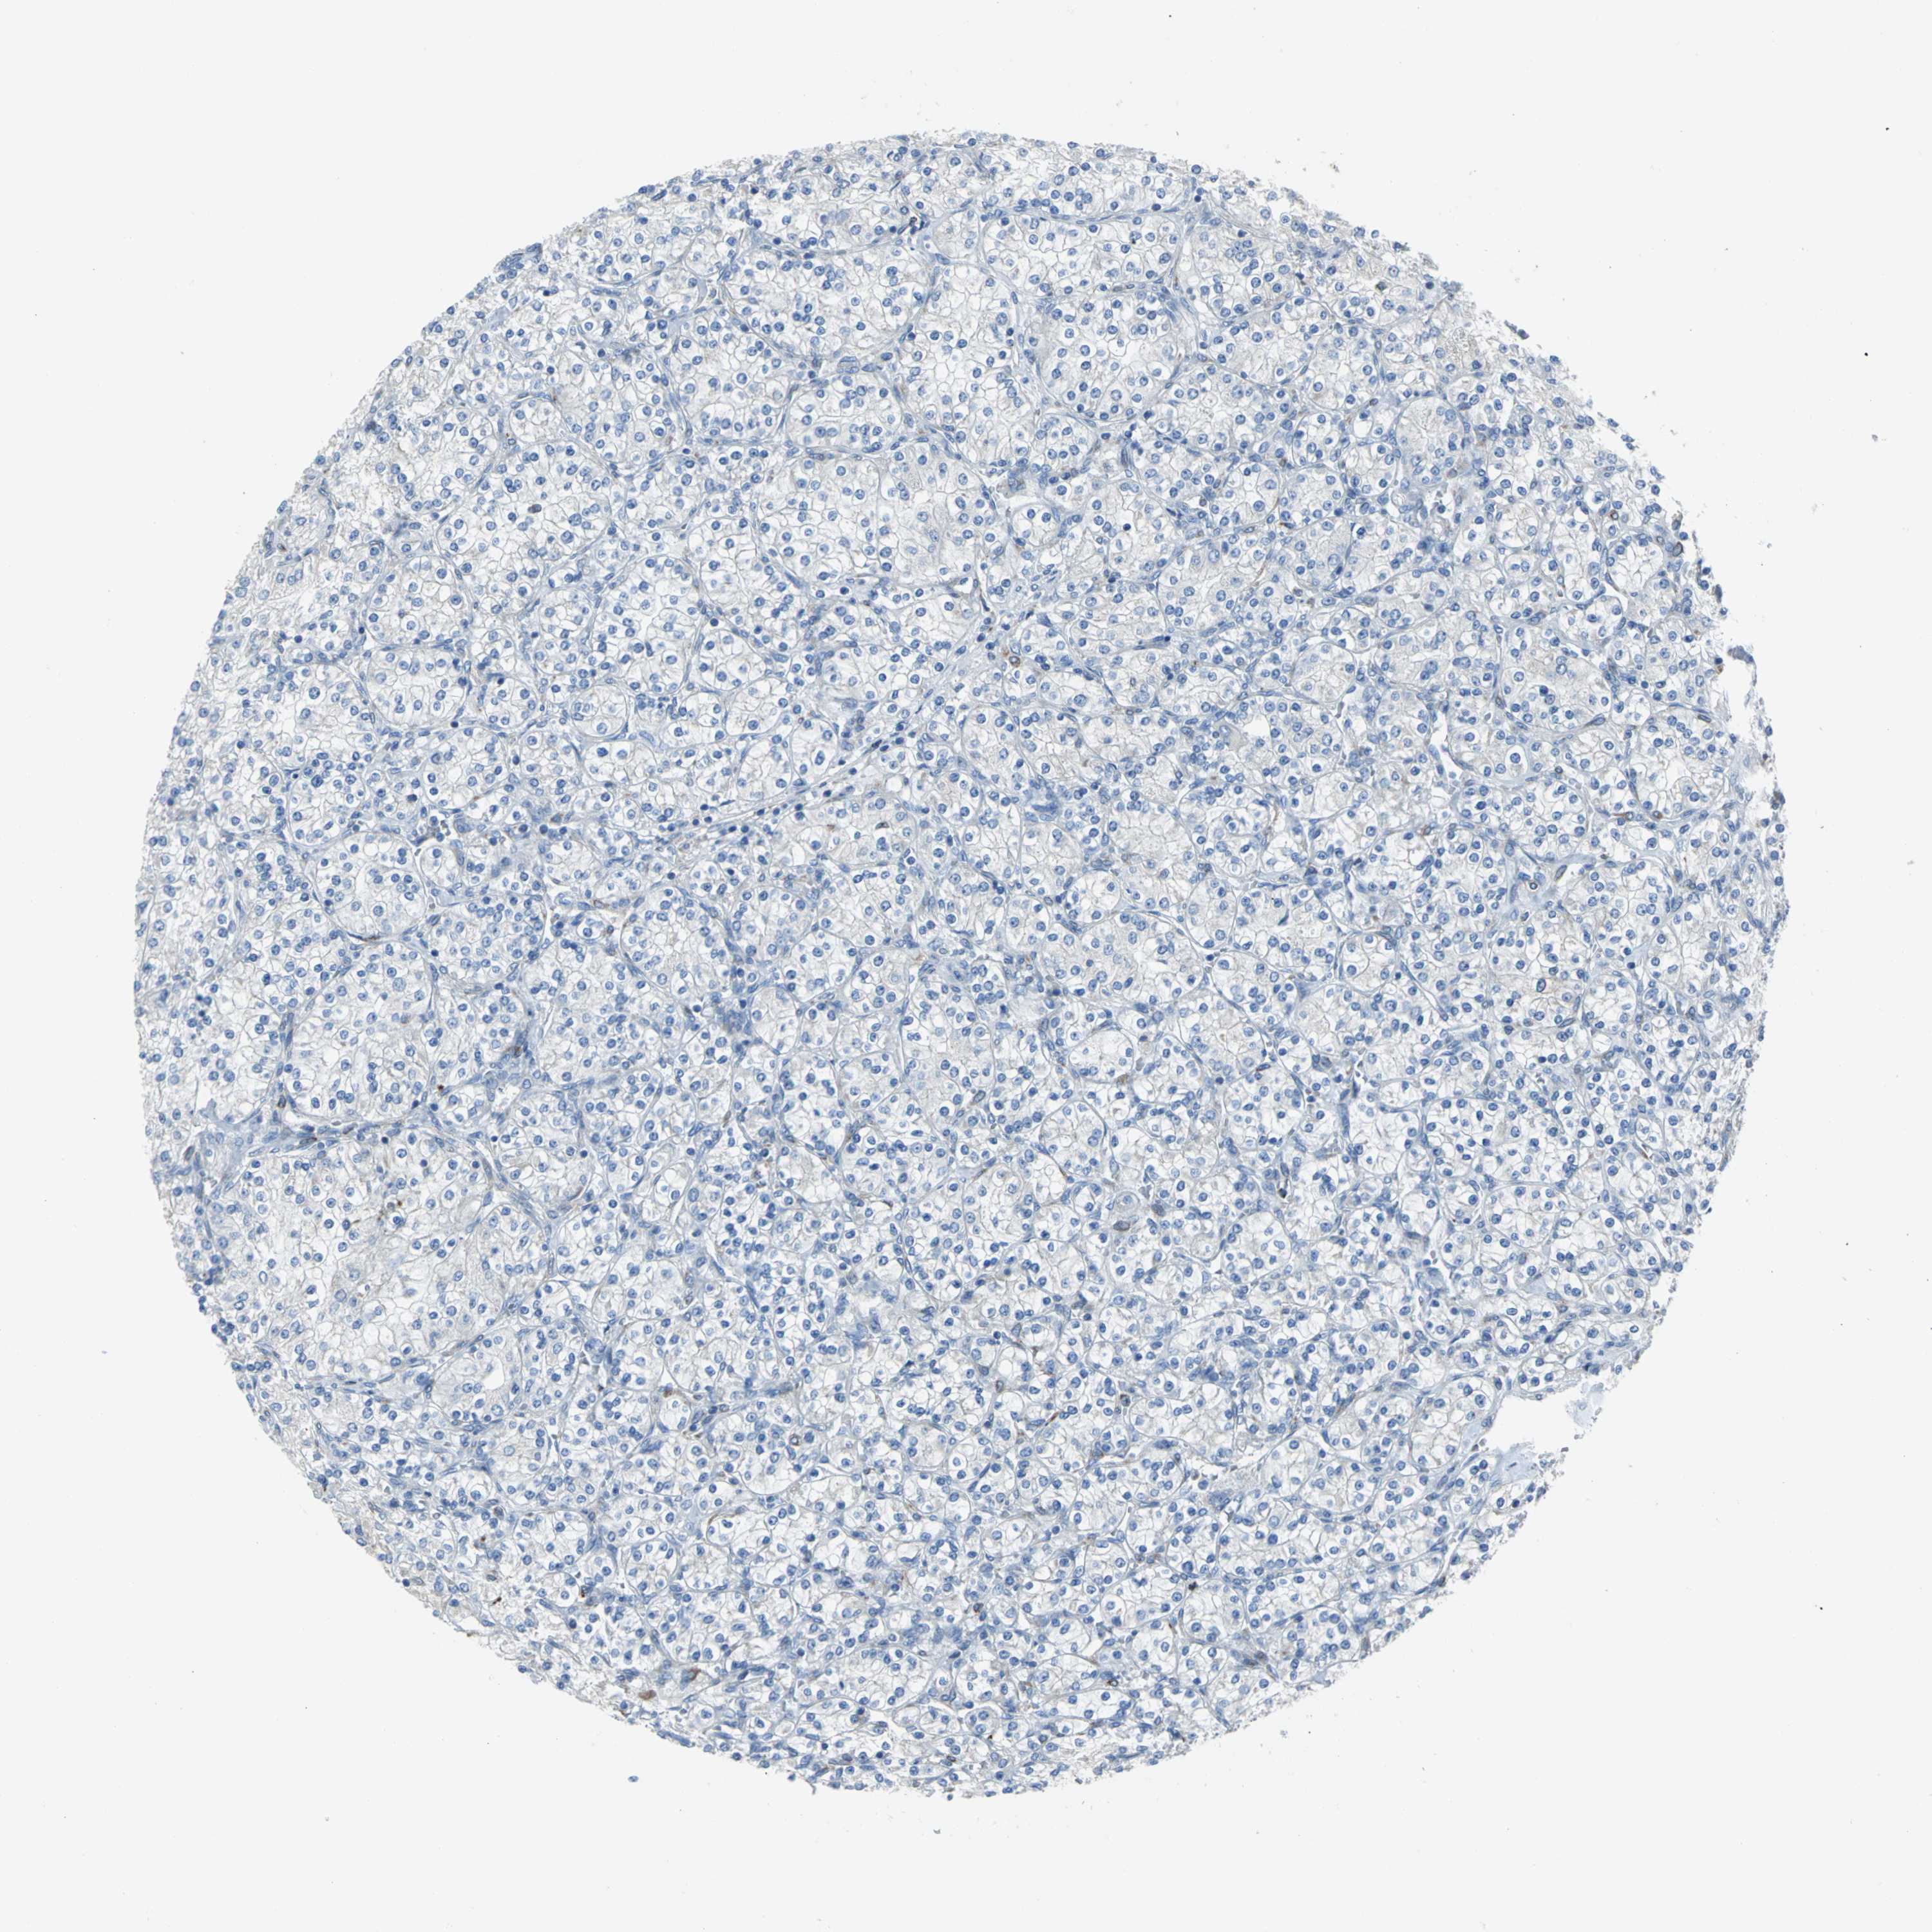

KIDNEY RENAL CLEAR CELL CARCINOMA (TCGA) - Interactive survival scatter ploti

The Survival Scatter plot shows the clinical status (i.e. dead or alive) for all individuals in the patient cohort, based on the same data that underlies the corresponding Kaplan-Meier plots. Patients that are alive at last time for follow-up are shown in blue and patients who have died during the study are shown in red.

The x-axis shows the expression levels (FPKM) of the investigated gene in the tumor tissue at the time of diagnosis. The y-axis shows the follow-up time after diagnosis (years). Both axes are complimented with kernel density curves demonstrating the data density over the axes. The top density plot shows the expression levels (FPKM) distribution among dead (red) and alive patients (blue). The right density plot shows the data density of the survived years of dead patients with high and low expression levels respectively, stratified using the cutoff indicated by the vertical dashed line through the Survival Scatter plot. This cutoff is automatically defined based on the FPKM cutoff that minimizes the p-score. The cutoff can be changed by dragging the vertical line or by entering a cutoff value in the square labeled "Current cut-off".

Under the Survival Scatter plot the p-score landscape (black curve; left axis) is shown together with dead median separation (red curve; right axis). Dead median separation is the difference in median mRNA expression between patients who have died with high and low expression, respectively. It is calculated as follows: median FPKM expression of dead patients with high expression - median FPKM expression of dead patients with low expression. This is intended to aid the user in visually exploring custom cutoffs and the associated p-scores and dead median separation.

Individual patient data is displayed and can be filtered by clicking on one or more of the category buttons on the top of the page. Categories describing expression level and patient information include: high, low, alive, dead, female, male and tumor stages. The scale of the x-axis can be toggled between linear and log-scale by clicking on the "x log" button. Mouse-over function shows TCGA ID, patient information and mRNA expression (FPKM) for each patient.

& Survival analysisi

Kaplan-Meier plots summarize results from analysis of correlation between mRNA expression level and patient survival. Patients were divided based on level of expression into one of the two groups "low" (under cut off) or "high" (over cut off). X-axis shows time for survival (years) and y-axis shows the probability of survival, where 1.0 corresponds to 100 percent.

EIF5A is validated prognostic, high expression is unfavorable in Kidney Renal Clear Cell Carcinoma (TCGA)

Best expression cut offi

Based on the FPKM value of each gene, patients were classified into two groups and association between prognosis (survival) and gene expression (FPKM) was examined. The best expression cut-off refers the FPKM value that yields maximal difference with regard to survival between the two groups at the lowest log-rank P-value. Best expression cut-off was selected based on survival analysis .

When clicking on this number, the vertical dashed line indicating cut-off, the interactive survival plot, and the Kaplan-Meier curve will be adjusted to show results based on the best expression cut-off.

: 208.36

TCGA RNA samplesi

RNA-seq data is reported as average FPKM (number Fragments Per Kilobase of exon per Million reads), generated by the The Cancer Genome Atlas (TCGA) .

Normal distribution across the dataset is visualized with box plots, shown as median and 25th and 75th percentiles. Points are displayed as outliers if they are above or below 1.5 times the interquartile range. FPKM values of the individual samples are presented next to the box plot.

Average pTPM 182.6

Number of samples 521